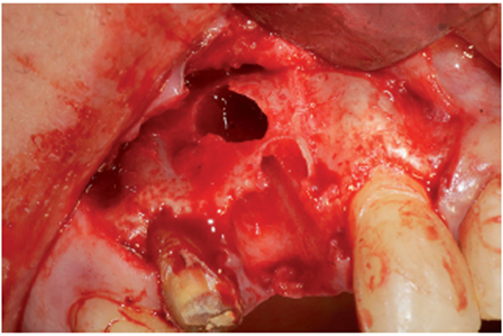

O procedimento cirúrgico foi iniciado através de uma anestesia infiltrativa com articaína 4%. Foram realizadas incisões relaxantes (Figura 4) para expor o leito cirúrgico e, consequentemente, a lesão periapical (Figura 5). Após o deslocamento do retalho, foi realizada a exodontia de forma atraumática (Figura 6) e na sequência, foi feita a curetagem do alvéolo removendo todo o tecido de granulação (Figura 7). Uma vez realizada a toalete do leito cirúrgico (Figuras 8 e 9), o implante Cone Morse Due Cone de 3.5 X 13 mm (Implacil De Bortoli) foi instalado seguindo o melhor posicionamento dentro do rebordo residual, conforme planejado (Figuras 10 e 11). Em sequência, foi realizada a instalação do Cover Screw (Figura 12) e o preenchimento do defeito ósseo com biomaterial (Bio-Oss 0,25), conforme figuras 13 e 14). O fechamento foi realizado com membrana de PTFE-d (Cytoplast TXT–200, Osteogenics – Lubbock TX, EUA), customizada para ser adaptada sobre o defeito ósseo, estendendo-se de 3 a 5 mm da margem do defeito ósseo e intencionalmente exposta (Figura 15). A sutura foi realizada com fio de PTFE (Cytoplast), como podemos observar na figura 16, e instalado um provisório adesivo na região (Figura 17).